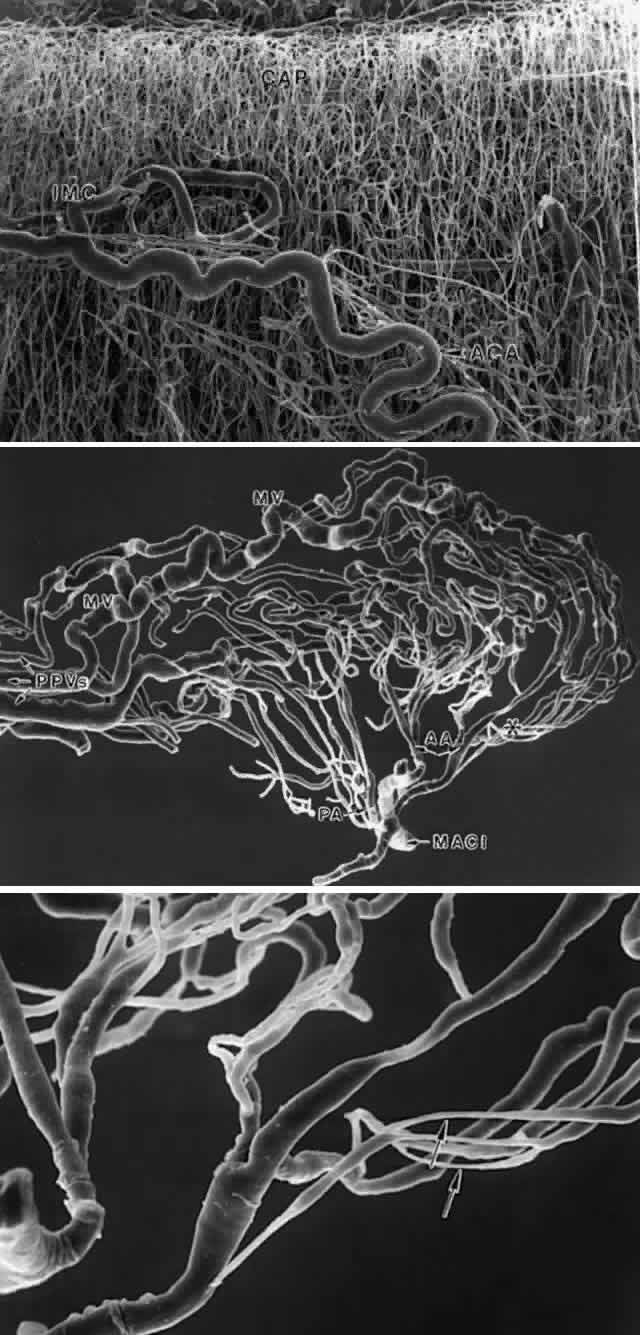

Studies on the ciliary body circulation, using scanning electron microscopy of methacrylate vascular casts, have greatly clarified this complex subject in recent years. The primate vasculature66–68 has been more extensively investigated than the human69,70but is sufficiently closely related to form a basis for understanding the human variations (Fig. 44). The blood supply to the ciliary body derives from two long posterior ciliary arteries and seven anterior ciliary arteries, two from each rectus muscle except for the lateral rectus, which provides only one. After leaving the rectus muscles, the anterior ciliary arteries send branches to form an anterior episcleral plexus around the corneal limbus.66,69 The remaining vessels divide into 10 to 20 branches before or after penetrating the sclera to enter the ciliary muscle, at the posterior border of the pars plicata. The lateral rectus vessel contributes only 0 to 2 branches. Within the ciliary muscle, an incomplete intramuscular circle or plexus is formed, primarily from branches of the anterior ciliary arteries with variable anastomoses to branches of the long posterior ciliary arteries.66–69 The intramuscular circle supplies particularly the outer and posterior part of the capacious capillary circulation of the ciliary muscle (see Figs. 44A, Figs. 45A) and sends recurrent branches back to join the peripheral choriocapillaris. Branches of the anterior ciliary arteries also supply the iris directly or from branches of the intramuscular circle and contribute to the major arterial circle of the iris.

Fig. 45. Scanning electron micrographs of human ciliary body vasculature after injection with methylmethacrylate. A. Anterior ciliary perforating artery (ACA) to intramuscular plexus (IMC), supplying the profuse capillary bed (CAP) of the anterior ciliary muscle. (X 54) B. Vasculature of a single ciliary process, supplied by anterior (AA) and posterior (PA) arterioles from the major arterial circle of the iris (MACI). The dilated marginal venules (MV) are clearly visible along the crest of the process and, along with a posterior venule, drain into three pars plana veins (PPVs). Many constricted segments seen in terminal arterioles to anterior and mid portion of the process. (X 96) C. Higher power view of constricted arterioles (arrows) to anterior edge of process. (X 300) (Courtesy of Dr. John Morrison)

The MACI is primarily concerned with supplying the extensive vascular plexus of the ciliary processes (see Fig. 44B). In the human, several arterioles from the MACI enter each process (Fig. 45B), forming what Funk and Rohen have described as three “vascular territories,” which occur also in other species and may have functional significance.69 The most anterior one is a small arteriolar-capillary network supplying the anterior edge and base of a major process with veins draining separately into the posterior pars plana. The second territory includes some arterioles continuing more or less directly into dilated venous capillaries traversing the crests of the processes where they enter into one or two large marginal venules. These marginal venules continue into the pars plana as large parallel pars plana veins, and in the choroid empty directly into the vortex veins. Other arterioles in the second territory supply the central portion of the ciliary processes as a network of venous capillaries, eventually opening into the marginal venules. The third vascular territory involves arterioles from the MACI perfusing the posterior third of the major processes and emptying also into the marginal venules. The minor ciliary processes are supplied similarly by these posterior vessels.

The arterioles supplying the anterior processes in the first and second territories often show long, constricted segments (100 to 120 μm in length)67–69 as they enter the processes (Fig. 45C). These sites are markedly enhanced by epinephrine, which can completely prevent perfusion of the vessels in both primates and humans.68,69 The posterior circulation does not have arteriolar constrictions responsive to epinephrine but has many anastomoses with the capacious capillaries of the ciliary muscle. The more highly specialized vasculature of the anterior ciliary body is undoubtedly related to aqueous secretion. Its epinephrine-sensitive regions may be the sites shown by immunostaining to contain adrenergic nerves harboring VIP (vasoactive intestinal peptide)-like terminals.72 These terminals have been noted particularly around large arterioles in the anterior ciliary body and anterobasal region of the processes and are thought to be important for regulation of aqueous secretion.